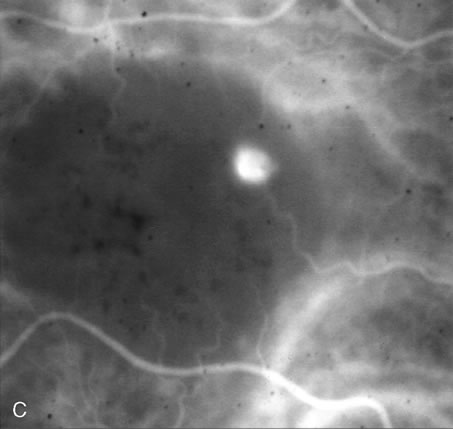

Although several authorities consider CSC to be a relatively benign disease,84 some patients develop recurrent, chronic neurosensory detachments that slowly cause photoreceptor degeneration. These patients often have a diffuse RPE “ooze,” reflecting generalized RPE dysfunction (Fig. 30). Their persistent neurosensory detachment can eventually lead to significant visual loss.85

Fig. 30. Diffuse retinal pigment epitheliopathy variant of central serous chorioretinopathy (CSC). Repeated episodes of acute CSC can result in chronic retinal pigment epithelium dysfunction with “ooze” of fluorescein. Unlike acute CSC, this uncommon variant often causes substantial loss of central vision.